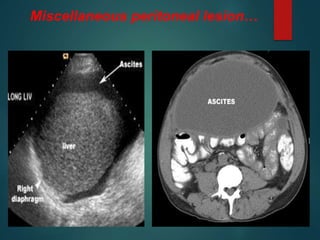

Miscellaneous peritoneal lesion…

Pneumoperitoneum…

Hemoperitoneum….